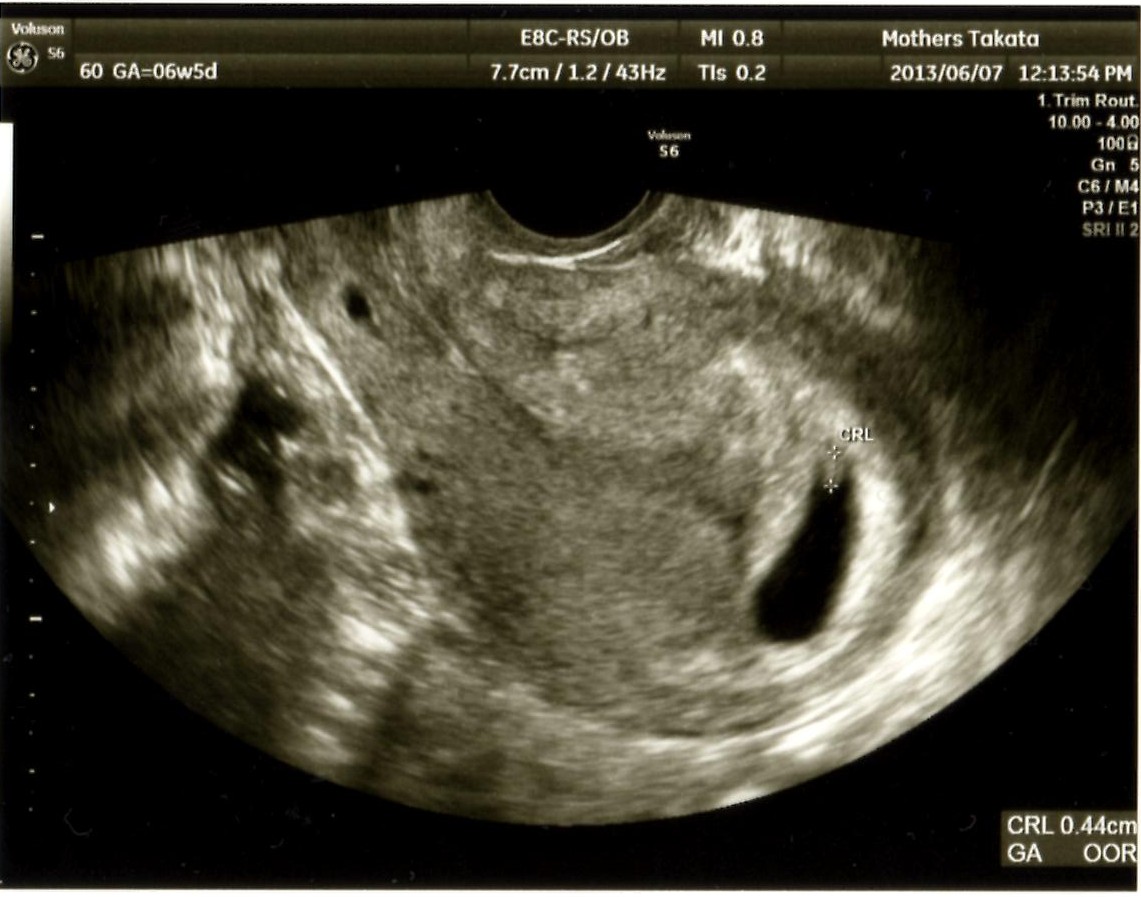

先週、検査薬で陽性がでて、

昨日、病院で確定してまいりました。

ベビー発生です。

そして、6週目にしてすでにツワってる。

確定したのは昨日だけど、もう1週間ちかく具合が悪くて、